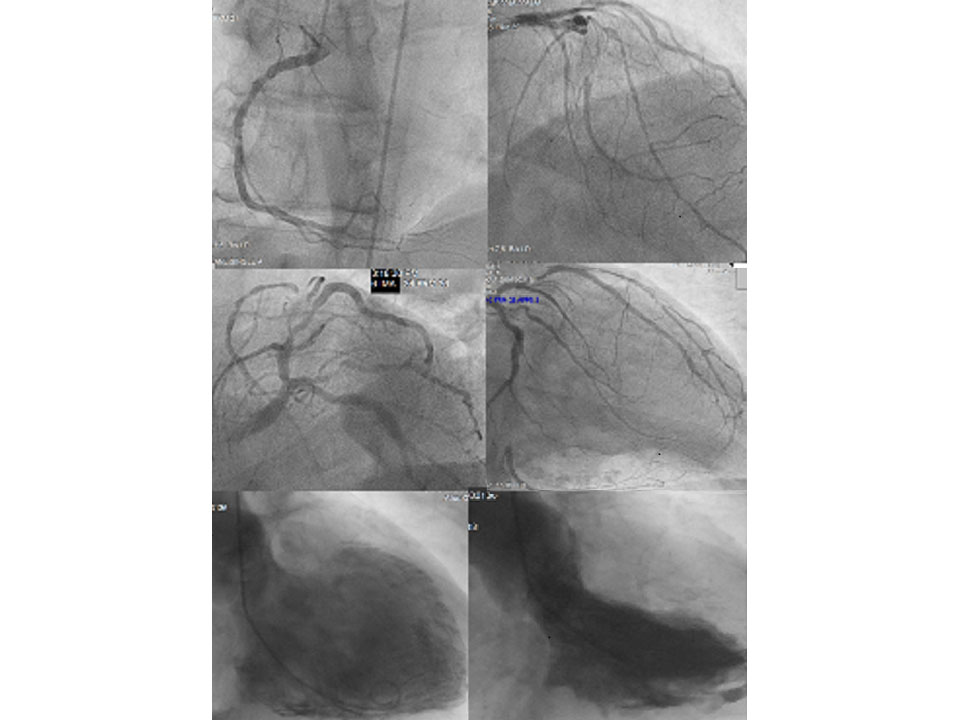

The image shows the current state of the coronary arteries of a 78-year-old patient who was recommended a bypass (3 bypasses) 37 years ago — which he declined. He quit smoking, lost weight, and walked 10-15km daily.

Coronary angiography shows numerous smaller vessels that developed as natural bypasses to supply regions where narrowed or blocked arteries did not deliver enough blood.

He has good heart pump function and a normal quality of life.